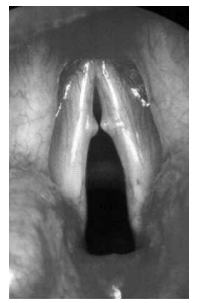

Qual alteração está comumente relacionada à lesão apresentada na laringoscopia a seguir?